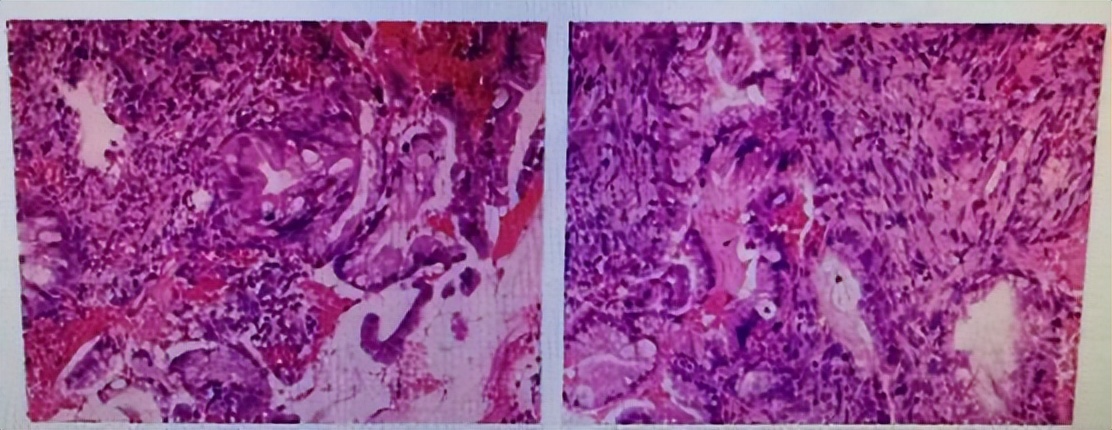

最后,宫颈活检病理结果回示: (宫颈组织)符合腺癌。

图 1